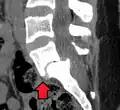

Anterolisthesis L5/S1 -

Anterolisthesis L5/S1. Blue arrow normal pars interarticularis. Red arrow is a break in pars interarticularis. -

Anterolisthesis L5/S1

Computed tomography (CT)

Computed tomography can be helpful in evaluating bony vertebral abnormalities, such as fractures.[38] This can be helpful in determining if the fracture is a new, old, and/or progressing fracture.[38] CT use in spondylolisthesis evaluation is controversial due to high radiation exposure.[39]